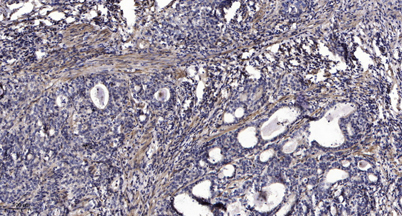

| Dilutions: | WB 1:500-2000;IHC-p 1:50-300; ELISA 2000-20000 |